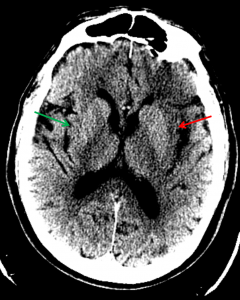

Sample ReportLoss of gray-white differentiation between the left insular cortex and external capsule (insular ribbon) concerning for acute left MCA territory ischemia. This suspicion is supported by subtle loss of gray-white differentiation in the remainder of the left MCA distribution with slightly increased density of the proximal left MCA relative to the right. Recommend brain MRI for further evaluation. No evidence of hemorrhagic transformation, mass effect, or hydrocephalus.

Loss of the insular ribbon on the left (red arrow) contrasted with normal insular ribbon on the right (green arrow)